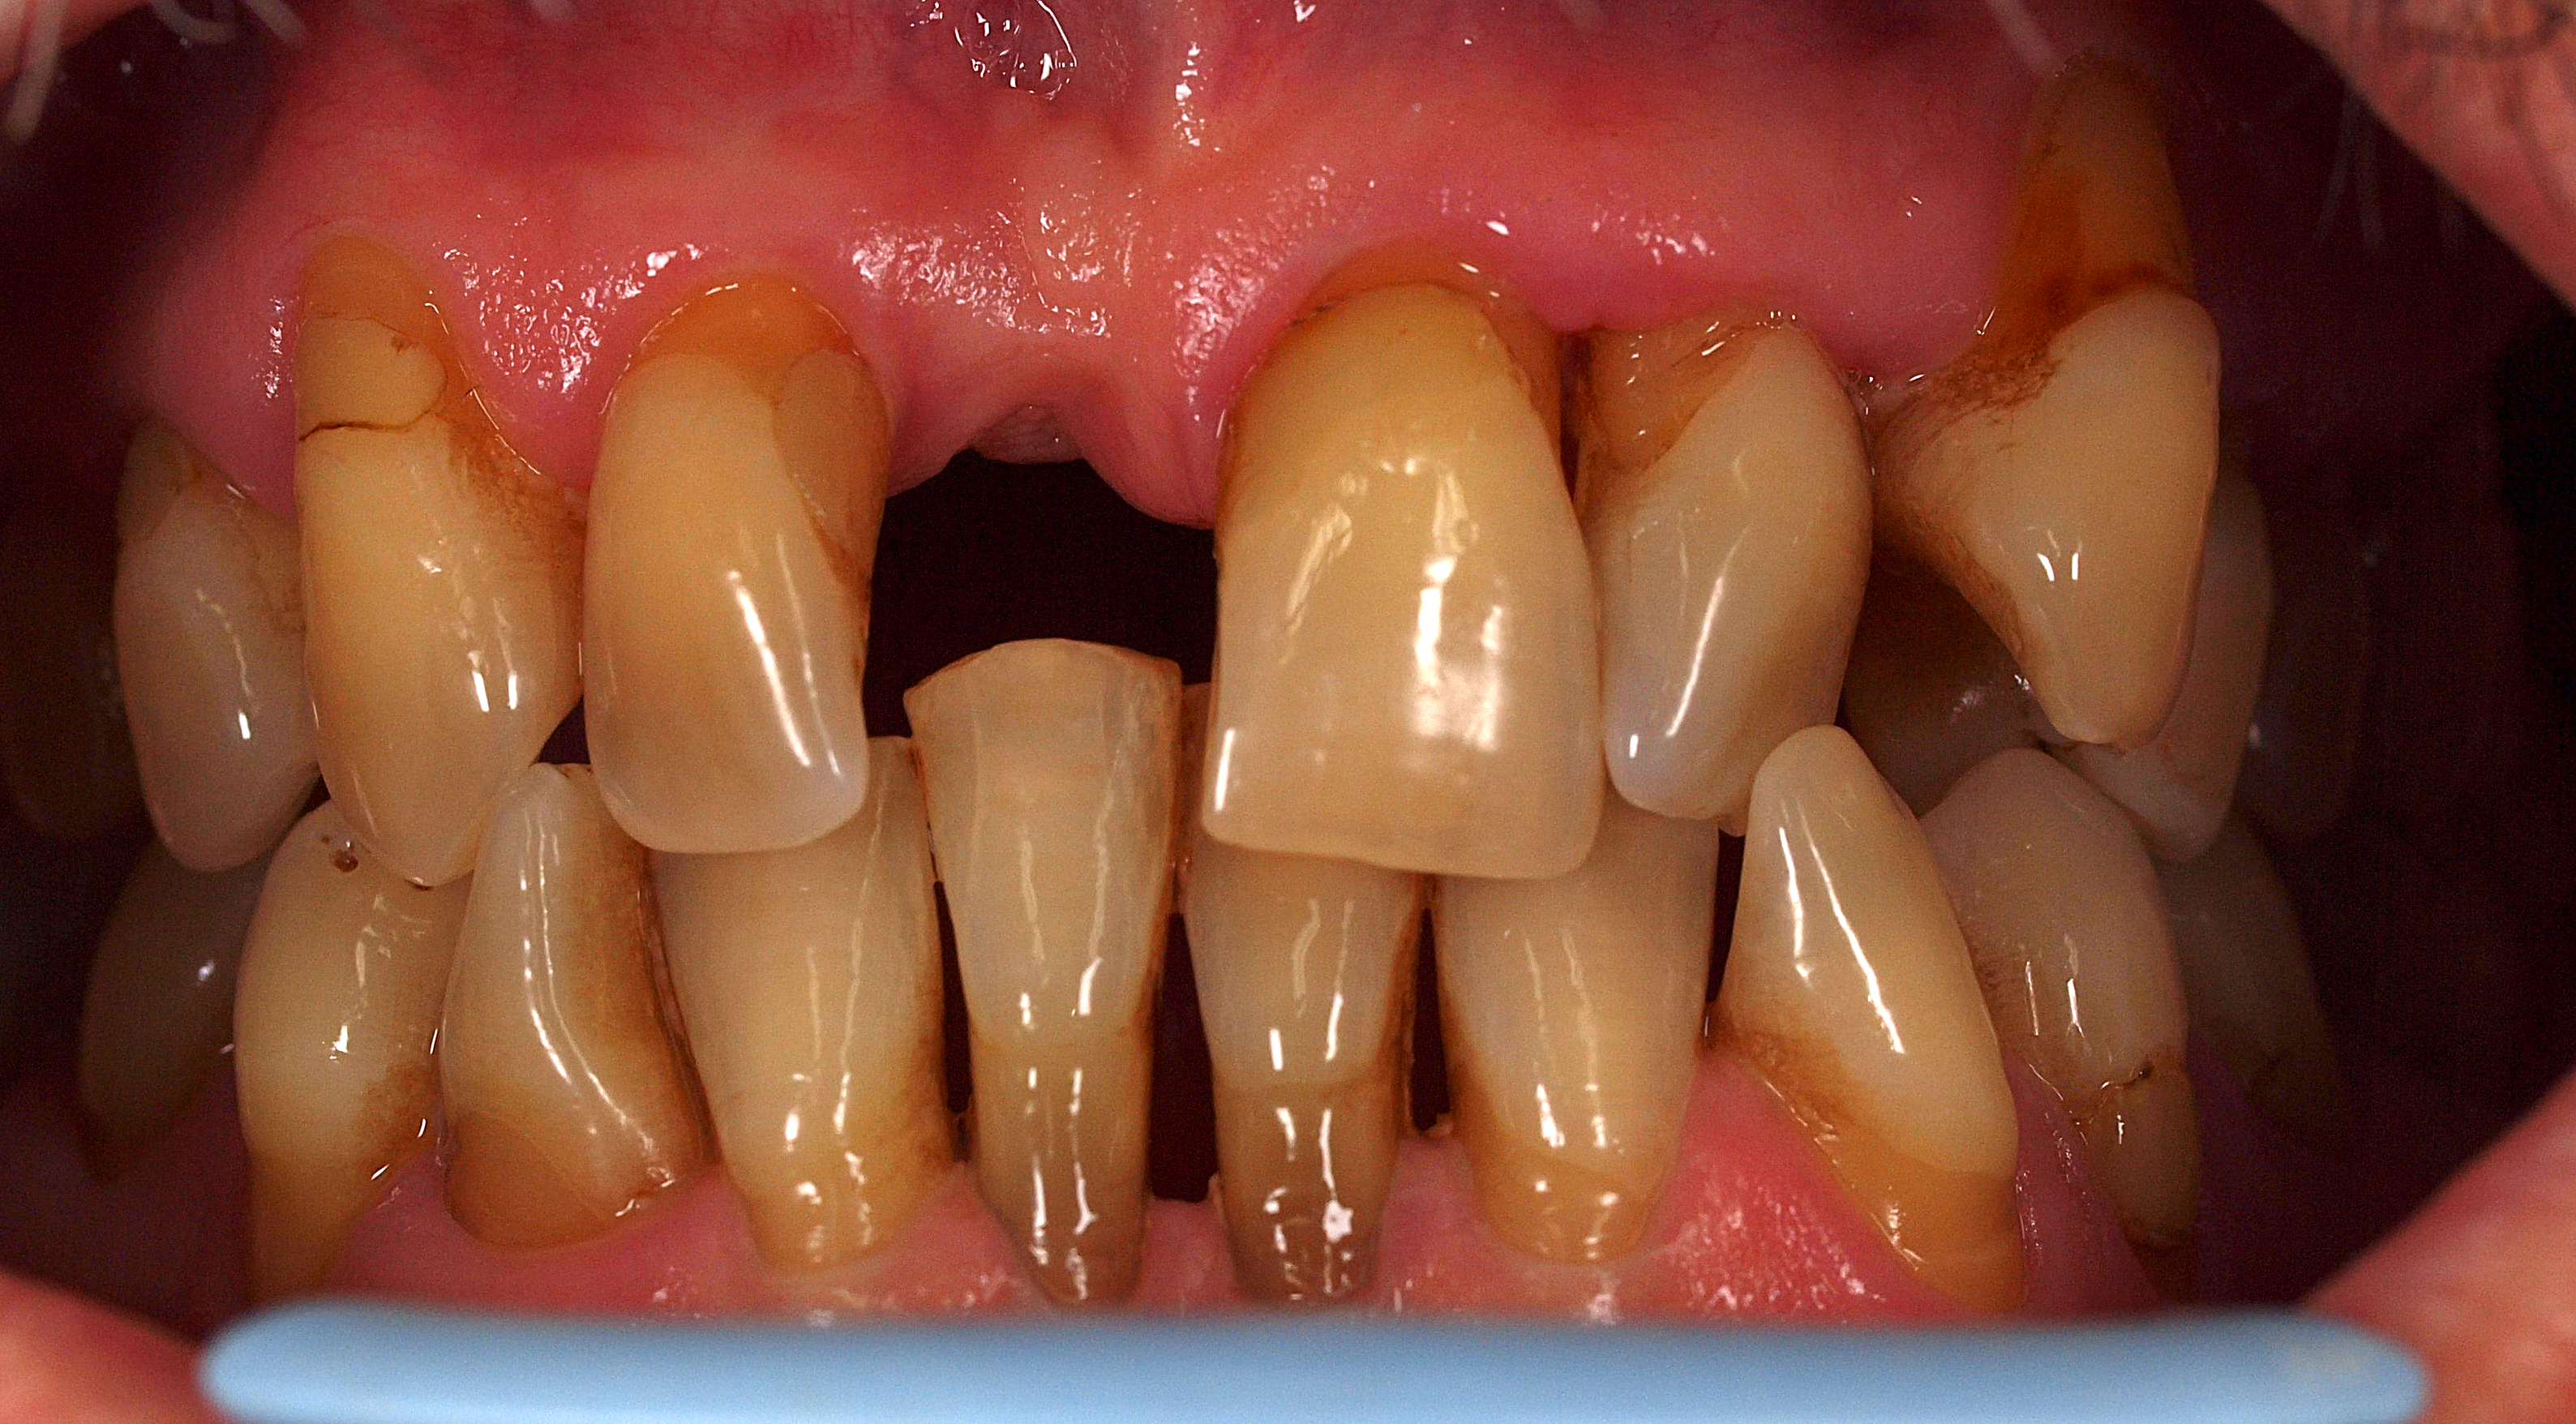

Przypadek 5.

Kategoria: 6. MOSTY KOMPOZYTOWE

Wykonanie mostu adhezyjnego w odcinku przednim przy zachowanych zdrowych i wolnych od wypełnień zębach zamykających lukę nie stanowi problemu, jeśli istnieje przestrzeń dla umieszczenia podparcia na powierzchniach podniebiennych. U prezentowanego pacjenta kontakty zwarciowe oraz przemieszczony ząb 41 stwarzały szczególnie niekorzystne warunki. Użytkowana przez blisko 20 lat proteza osiadająca, tzw. klips, zapewniała wygląd, ale powodowała poważne problemy podczas uwielbianego przez pacjenta biegania przełajowego. Z zastrzeżeniem warunkowego charakteru pracy podjęto próbę stworzenia mostu osadzonego adhezyjnie wyłącznie na powierzchniach stycznych 12 i 21. Do wzmocnienia zaplanowano wykorzystanie maty szklanej, której kształt miał odwzorować podczas pomiarów płatek bibułki. Po ustabilizowaniu maty szklanej i stworzeniu przęsła mostu podłożono pasek celuloidowy i wymodelowano powierzchnię dodziąsłową. Po zakończeniu modelowania, dobarwieniu i polimeryzacji warstwy szkliwnej powierzchni licowej paseczkiem ściernym wygładzono kontur. Polerowanie konturów wykonuje się nitką Super Floss, co pozwala zademonstrować pacjentowi metodę prowadzenia zabiegów higienicznych. Przestrzenne ustawienie zębów w zwarciu wymusza nieznaczną protruzję przęsła, co w opinii autora nadaje całości bardzo naturalny wygląd. Pacjent z zadowoleniem zaakceptował wygląd pracy. Zastosowanie intensywnego koloru opakerowego w rejonie dodziąsłowym doskonale imituje profil wyłaniania korony zęba – przęsła mostu.